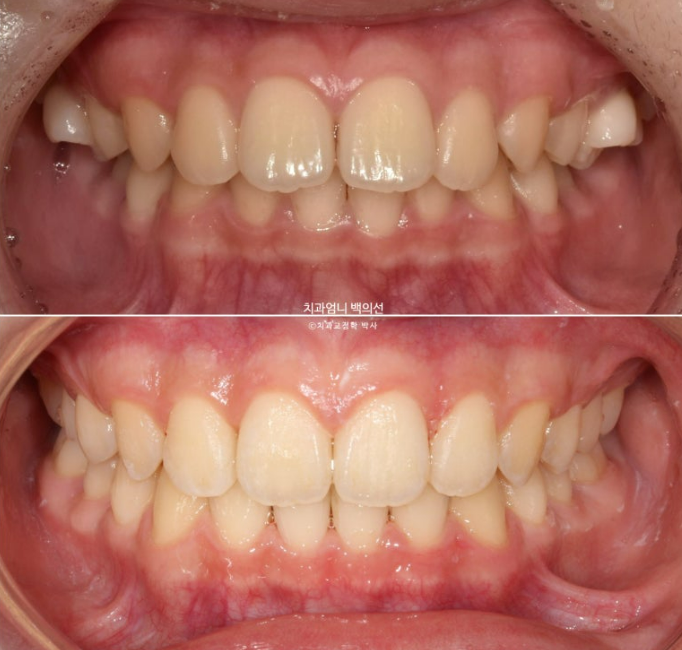

24.03~25.05

24.03

작년 봄, 교정치료를 위해 내원한 만 10세 어린이입니다.

위 앞니가 아랫니를 많이 덮어 깊게 물리는 과개교합이 보입니다.

위 앞니 돌출이 보입니다.

남아있는 유치 두 개가 가위교합입니다.

첫세트의 장치는 22개가 나왔습니다. 24년 3월부터 24년 9월까지 첫세트의 장치를 모두 낀 후 모습입니다.

24.09

앞니 돌출은 해결이 되었으나 앞니가 깊게 물리는 과개교합이 남아있습니다.

25년 5월 두번째 세트 21개 장치를 모두 낀 후 드디어 치료를 마무리 했습니다.

25.05

앞니 깊게 물리는 과개교합은 해결이 되었고 중심선은 잘 맞습니다.

어금니 교합은 1급 교합관계입니다.

이제 전 후 비교해보겠습니다.

총 치료기간은 1년 2개월 입니다.